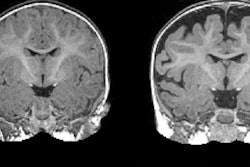

MRI revealed a hyperexpansion of the brain's surface area from 6 to 12 months in babies who developed autism, compared with babies who did not show evidence of the condition at 24 months of age. The increased growth rate of surface area during the infant's first year was associated with an increased growth rate of overall brain volume in the second year. That brain "overgrowth" was tied to the emergence of autistic social deficits in the second year.

With their data on brain volume, surface area, and cortical thickness at 6 and 12 months of age, as measured by MRI, the researchers then used a computer program to generate a way to classify babies most likely to meet criteria for autism at 24 months. The computer algorithm was tested on a different group of study subjects.